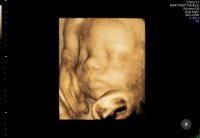

Og jeg er evig takknemlig for at alt ser helt perfekt ut på UL i dag med skikkelig anatomisk gjennomgang, fra hodet til tær, og alt som var fryktelig galt er helt perfekt nå. Er 12+2 i dag, men jordmor målte meg til 12+4, så termin rundt 28 april. Spent på om sykehuset finner det samme på ultralyd neste onsdag. Enn hvor glad jeg er for at jeg har en frisk lillebror i magen, så er jeg ett lite snev skuffet. Skuffet over at jeg ikke får min lille prinsesse Maja, som jeg alltid har drømt om. Vet at jeg blir like glad i lillebror som jeg er i storebror og gutt kan jeg jo, men jeg drømte liksom om å få en jente. Men min jente var syk…

21+4 og tiden går både fort og sent på samme tid…